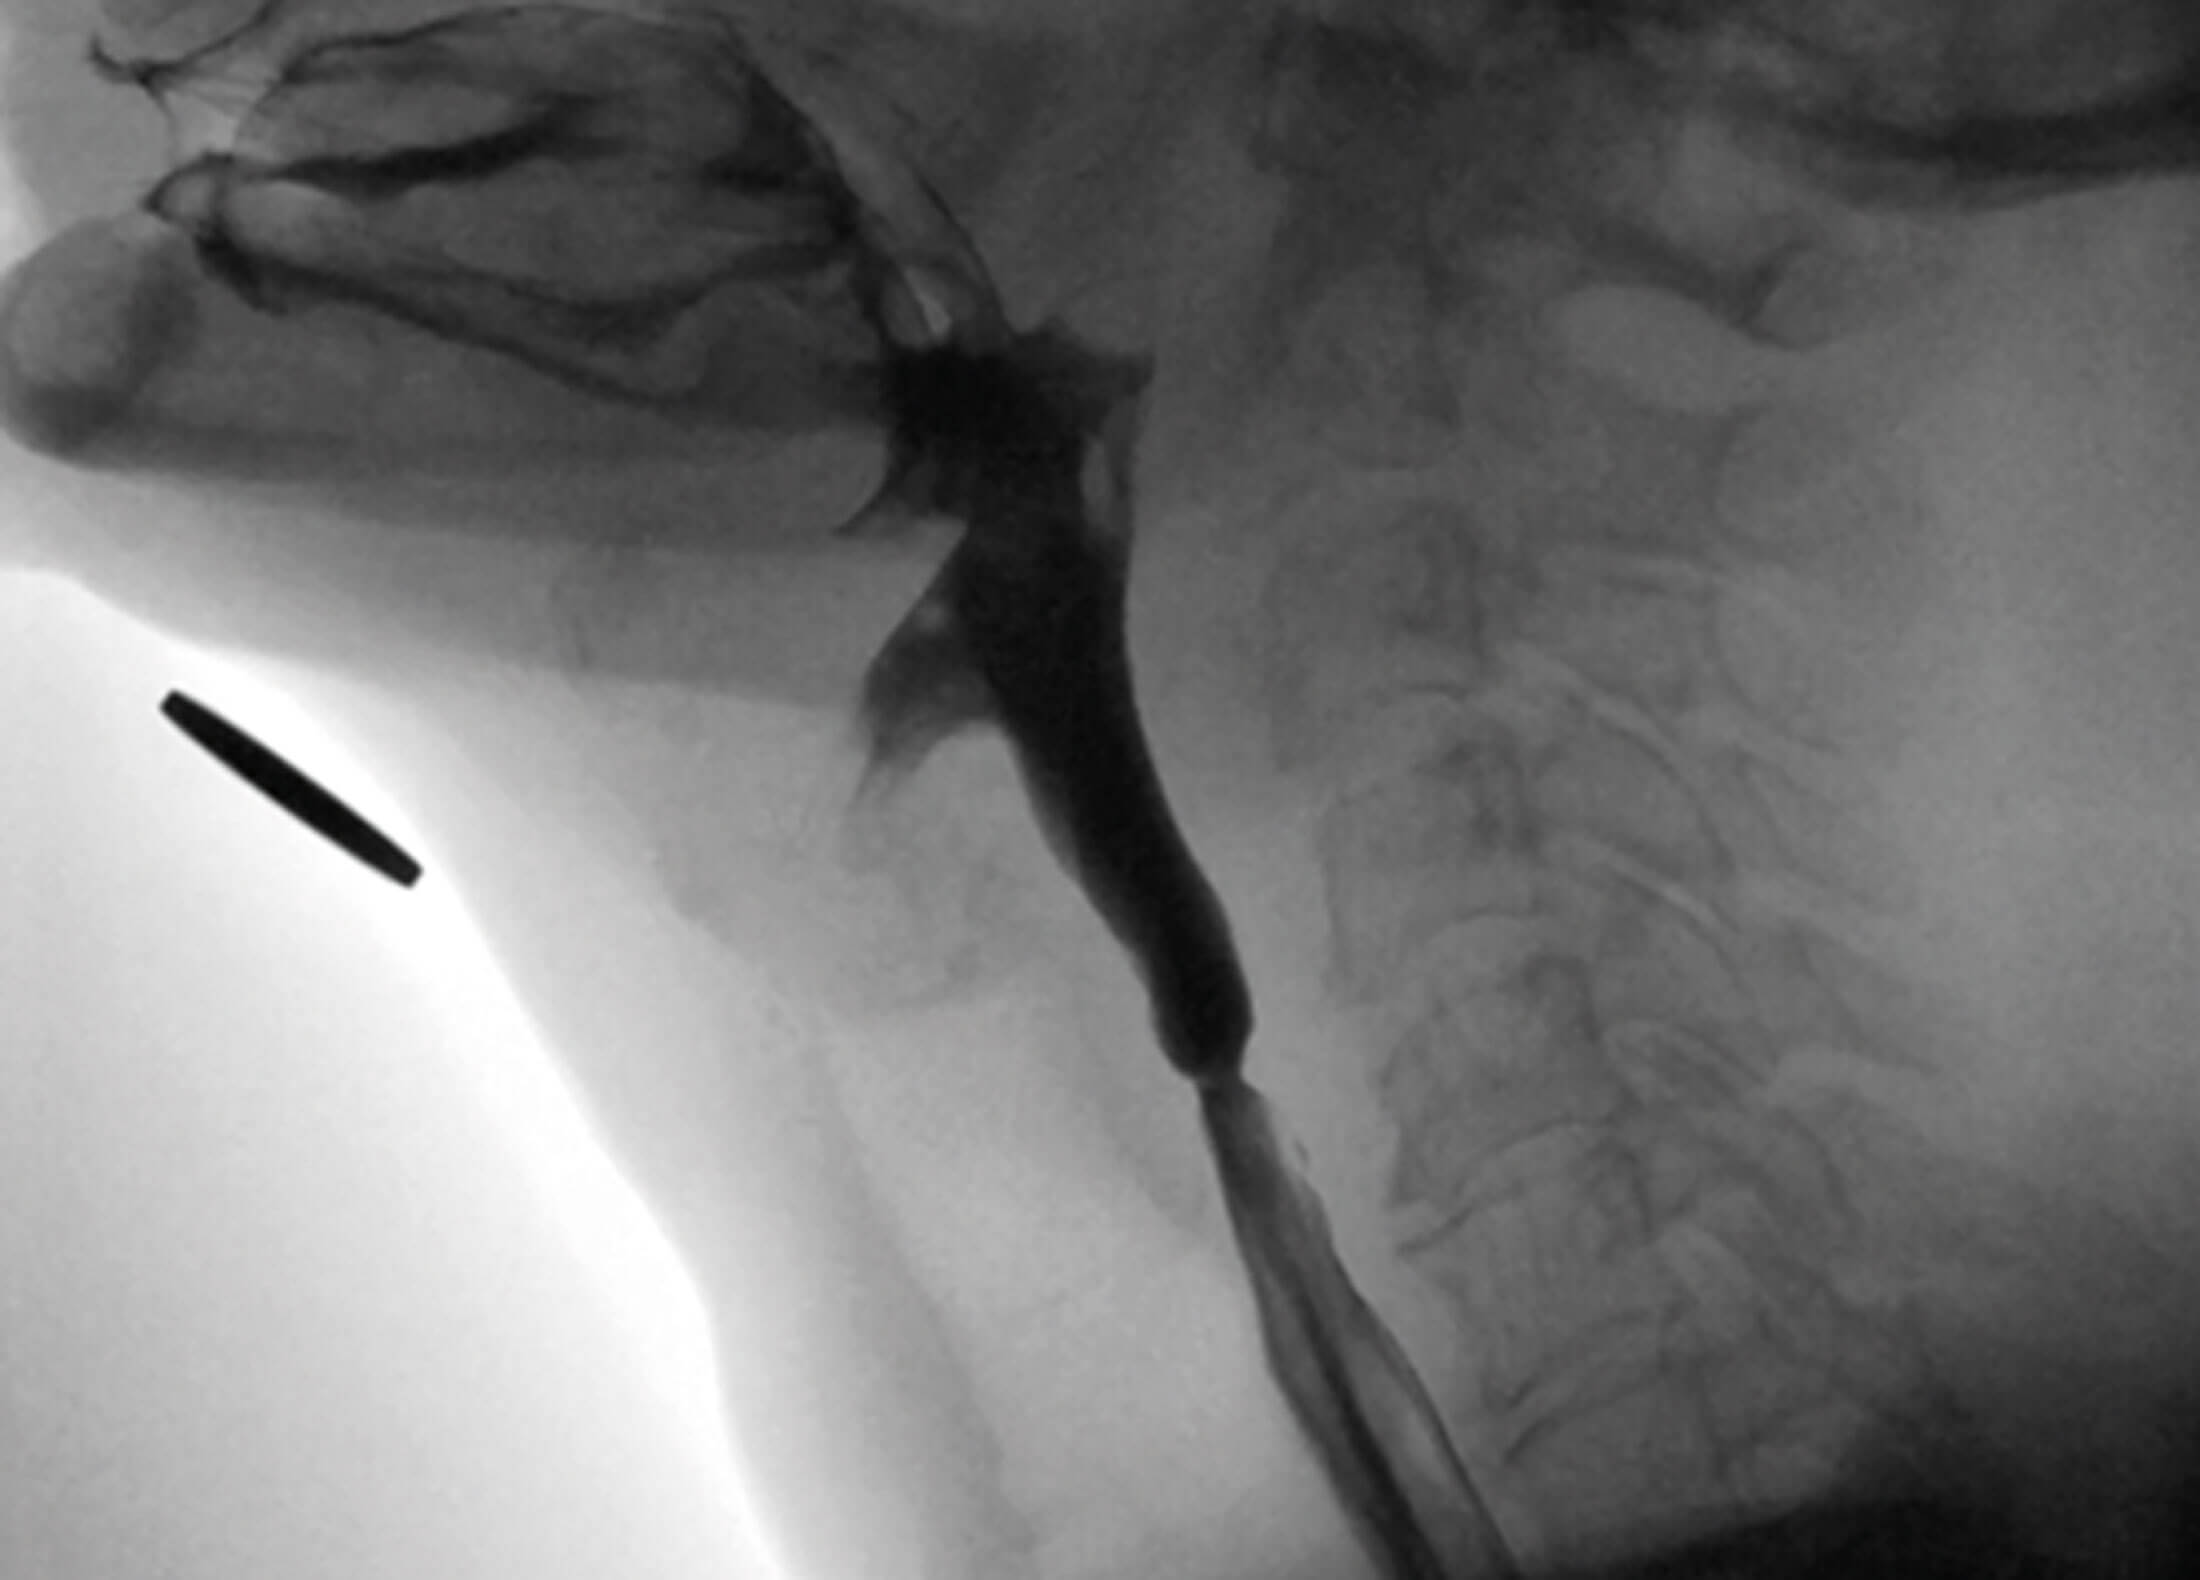

Fluoroscopic lateral view of pharyngoesophageal segmaent

demonstrating upper oesophageal sphincter web.